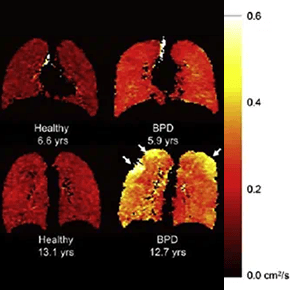

Neonatal MRI

The goal of this research is to translate new and innovative MRI techniques to sick and challenging patient populations, like those that are born prematurely. Our studies include both proton MRI and hyperpolarized gas MRI in infants. This has begun to revolutionize our understanding of both parenchymal and airway components of disease. This research is being conducted in partial collaboration with the BPD Center.